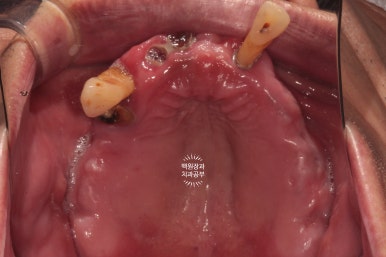

교합면에서 촬영한 사진입니다.

치아를 다 발치해야겠다는 생각이 절로 드는 환경이셨어요.

혹시나 보이시나 모르겠지만, 상당히 잇몸뼈가 얇음이.. 예상되는 상태였습니다.